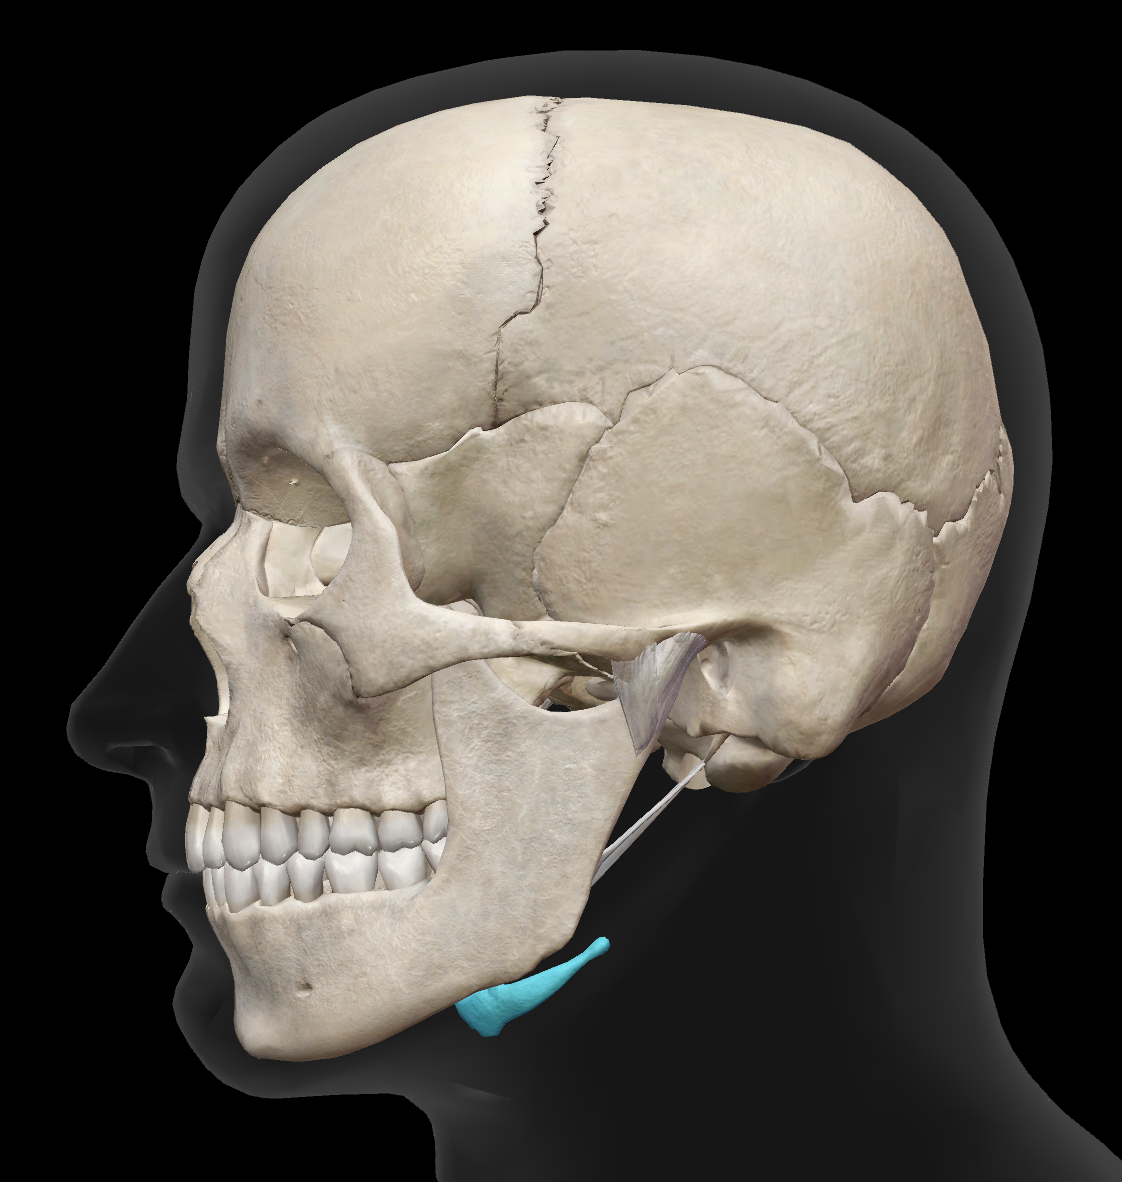

What bone is this?

mandible

What is the name of this bone?

hyoid bone